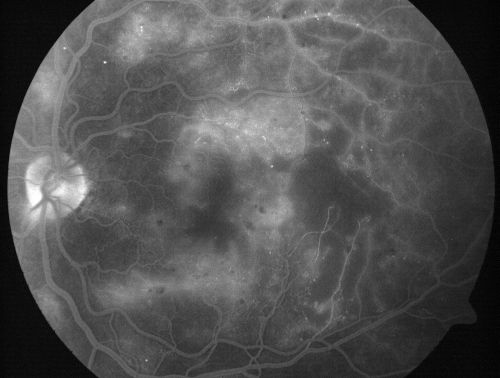

Capillary Non-Perfusion - Severe Non-Proliferative (Background) Diabetic Retinopathy - Type I - 20 Year Old Man Diabetic 16 years

20 year old diabetic with poor vision for the past three or four years. He has been diabetic for sixteen years and hemoglobin A1C of 10.0.   20/25 OD, 20/30 OS.